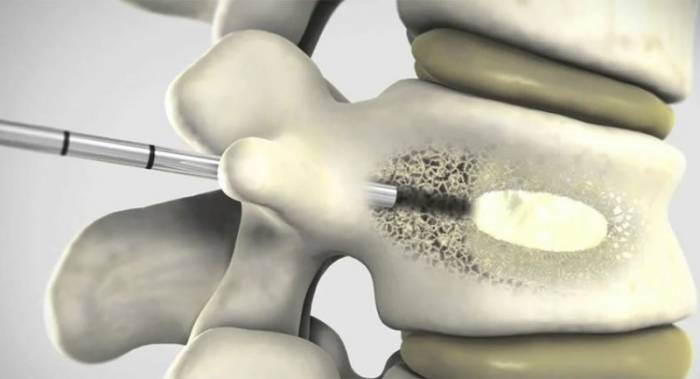

| Этап 2: операционный процесс | В ходе операции, в области локализации повреждения осуществляется прокол, через который вводится специальная металлическая трубка. В трубку пропускается игла, при помощи которой берется проба костной ткани. Изучив костный образец, лечащий врач вводит в поврежденную область специальный баллончик, наполненный контрастирующим веществом. Оно необходимо для того, чтобы обеспечить возможность слежения за ходом операции при помощи специальных приборов. Также, контрастирующая жидкость формирует мышечный каркас, позволяющий правильно заполнить полости медицинским цементом. Цемент вводится в поврежденный участок после изъятия контрастирующего вещества и извлечения баллончика. Застывает медицинский цемент быстро, в течение 6-10 минут |

Метод имеет среднюю степень инвазивности. В ходе процедуры ткани травмируются незначительно, поскольку через кожный покров с микроразрезом тканей, в поврежденный заболеванием или травмированный позвонок вводится скрепляющее его вещество – цементная смесь (полиметилметакрилат). Вещество застывает, позвонок укрепляется.

- Суть процедуры в том, чтобы ввести в позвоночное тело цемент, минимально повредив кожу и ткани. Для этого через кожу вводится металлическая игла.

- Она движется, минуя отростки и связочные дуги, направляясь прямо к сломанному позвонку, в котором из-за перелома образовалась трещина.

- Через эту трещину в позвонок вводится цементирующее вещество.

Смесь начинает застывать на шестой минуте, а через одиннадцать застывает полностью. За это время хирургу необходимо успеть равномерно заполнить тело позвонка цементом.

В процессе застывания полиметилметакрилат полимеризуется, нагреваясь при этом до 70°С. Это дает профилактику воспалений, воздействует уничтожающе на клетки опухоли, если таковая присутствует, и обеспечивает сцепку цемента с костной тканью.

Во время операции в тело поврежденного позвонка вводится металлическая игла. Через нее под флюороскопическим контролем врач вводит специальную смесь. В ее состав входят следующие компоненты:

- костный цемент, основанный на ПММА.

У хирурга есть 6 минут, чтобы ввести цемент в тело позвонка под специальной рентген-аппаратурой в скопическом режиме. Спустя 10 минут состав застывает, заполняя трещины и пустоты и укрепляя позвонок.

Вместе с полиметилметакрилатом в соединении, которым заполняется позвонок, имеется контрастный компонент. Контраст подсвечен на рентгене, поэтому заполнение контролируется с максимальной точностью. В костном теле позвонка цемент быстро застынет, заполнит все сегменты, где существуют деструктивные изменения.